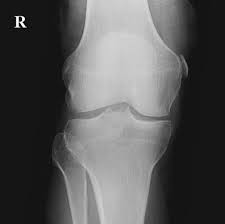

Pellegrini stieda syndrome is a medical problem which is characterized by pain, swelling and inflammation in the knee. It is a common incidental finding on knee radiographs. Pain and restriction of movements. The cause of the knee effusion is unknown. There is a moderately large knee effusion. The diagnosis pellegrini stieda disease was made. Is the presence of a radiological finding of calcification on the medial side of the knee as a consequence. It is likely that this patient has been an active sportsman in the past.

Pain and restriction of movements. The cause of the knee effusion is unknown. It is likely that this patient has been an active sportsman in the past. #foamed #foamrad #radiology #rad #elearnrad #voxelz #varunbabu #drbabu. Pellegrini stieda syndrome is a medical problem which is characterized by pain, swelling and inflammation in the knee. Most of the cases of pellegrini stieda lesions are not symptomatic, and pellegrini stieda syndrome is said to exist when the lesion becomes symptomatic i.e. Ayurvedic treatment is the natural way to treat pellegrini stieda syndrome. Is the presence of a radiological finding of calcification on the medial side of the knee as a consequence. The diagnosis pellegrini stieda disease was made. It is a common incidental finding on knee radiographs. With the ayurvedic treatment, it is possible to avoid surgery. This occurs due to the deposition of calcium on the inner side of the knee. Learn about this soft tissue calcification around the knee joint.

Pellegrini stieda syndrome is a medical problem which is characterized by pain, swelling and inflammation in the knee. The diagnosis pellegrini stieda disease was made. Learn about this soft tissue calcification around the knee joint. The cause of the knee effusion is unknown. There is a moderately large knee effusion. Pain and restriction of movements. Is the presence of a radiological finding of calcification on the medial side of the knee as a consequence. It is a common incidental finding on knee radiographs. Most of the cases of pellegrini stieda lesions are not symptomatic, and pellegrini stieda syndrome is said to exist when the lesion becomes symptomatic i.e. #foamed #foamrad #radiology #rad #elearnrad #voxelz #varunbabu #drbabu. It is likely that this patient has been an active sportsman in the past. There is evidence of osteoarthritis. This occurs due to the deposition of calcium on the inner side of the knee.